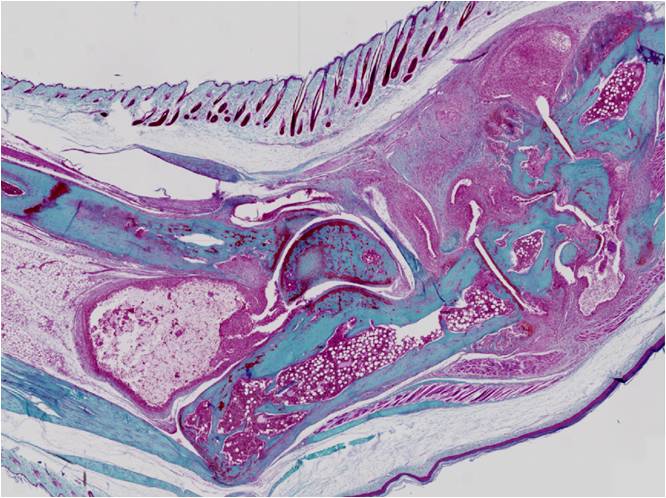

Histology of an ankle joint